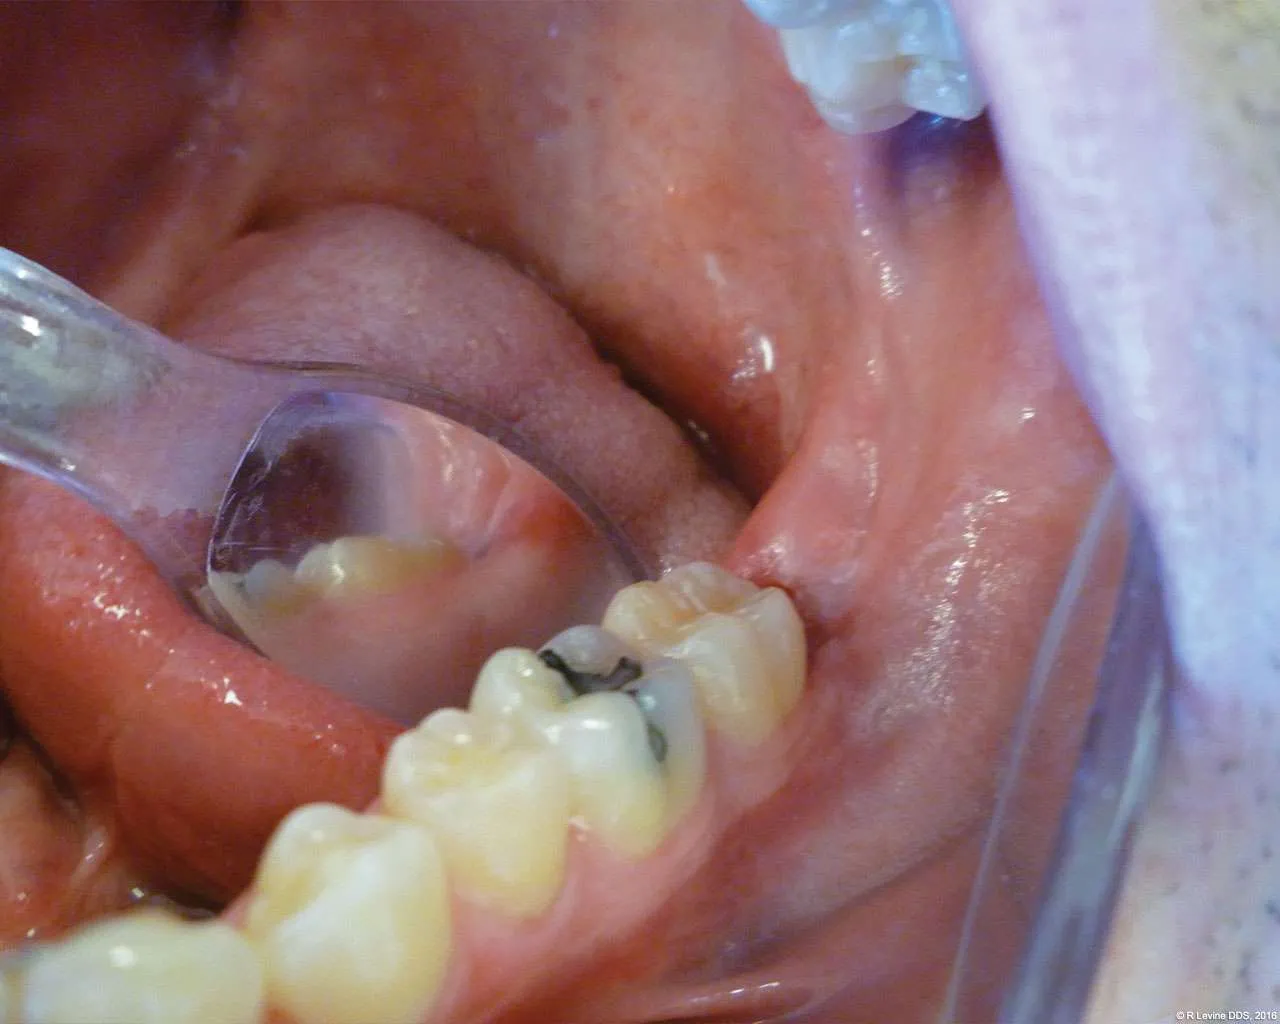

- After the initial pass with the laser, the inflamed gingiva bled slightly and the surgeon defocused the beam by increasing the nozzle-to-tissue distance to quickly obtain hemostasis (Figure 6). Note the excellent visualization and the clear operatory field.

- Additional tissue around the primary surgical site was superficially ablated to “feather out” the wound and make the treated area blend with the healthy gingiva better (Figure 7).